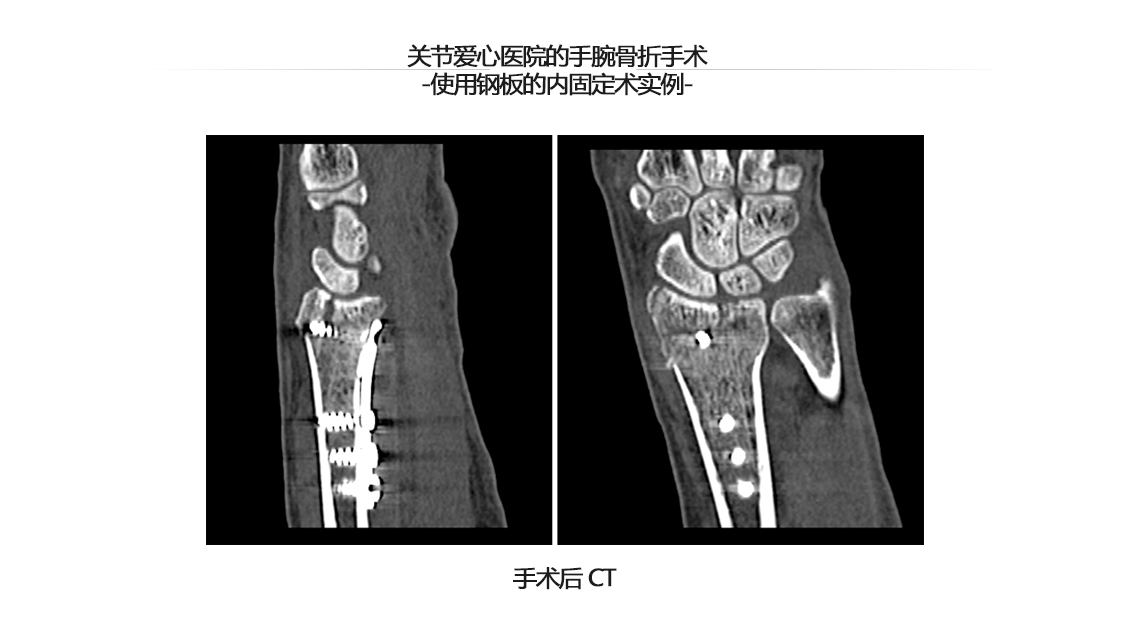

手腕关节骨折

手腕骨折手术